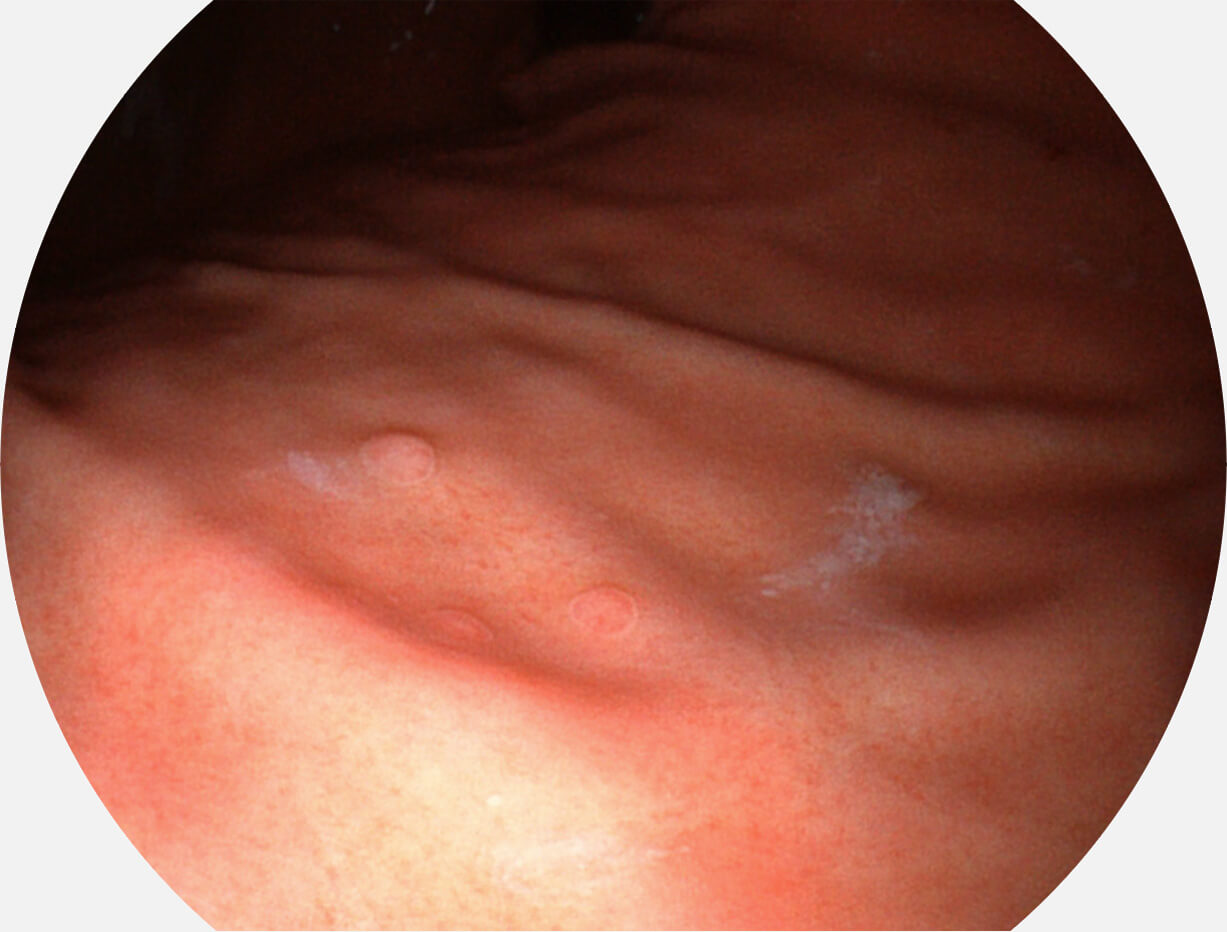

Spectral Focused lmaging, SFI

图像具有高亮度、高黏膜血管颜色对比度的特点,且不改变粘液、食物残渣、粪便的基本颜色,可在中远景下进行观察,助力消化道早期疾病的诊断。

SFI图像

采用光路合束技术,光谱自由度高,实现了更丰富的照明模式,染色模式SFI及VIST,从远景到近景,助力消化道早期疾病诊断。